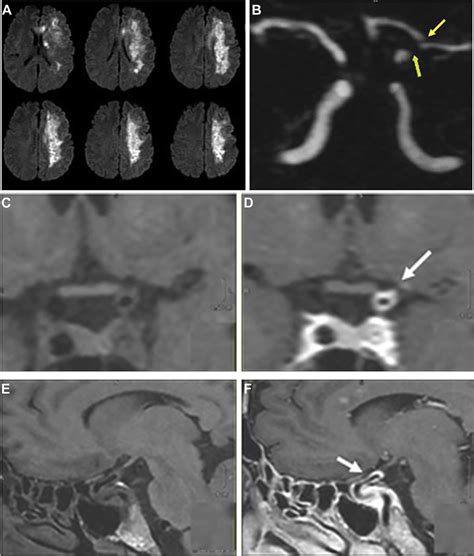

• Magnetic Resonance Imaging (MRI): MRI uses powerful magnets and radio waves to generate highly detailed images of the brain. It’s generally considered more sensitive than CT for detecting acute ischemic stroke, especially in the early stages. Different MRI sequences provide a wealth of information . For instance, diffusion-weighted imaging (DWI) is incredibly sensitive to the cytotoxic edema that occurs within minutes of an ischemic event, allowing for very early detection of infarction. Perfusion-weighted imaging (PWI) can assess blood flow through the brain tissue, helping to identify areas of compromised perfusion that might be salvageable. MRI angiography (MRA) is another technique used to visualize the blood vessels, similar to CTA but without the ionizing radiation. While MRI offers superior detail, it takes longer than a CT scan and may not be readily available in all emergency settings, and patients with certain implants might not be able to undergo the scan.

• Cerebral Angiography (DSA): Digital subtraction angiography is considered the gold standard for visualizing the cerebral vasculature. It involves inserting a catheter into an artery (usually in the groin) and guiding it up to the arteries in the brain, injecting contrast dye directly into the vessels. This provides extremely detailed, real-time images of blood flow and can precisely pinpoint blockages. DSA is typically reserved for cases where more information is needed before or during intervention , such as mechanical thrombectomy (clot removal). It’s highly invasive compared to CT or MRI, but it offers unparalleled detail and allows for immediate therapeutic intervention.